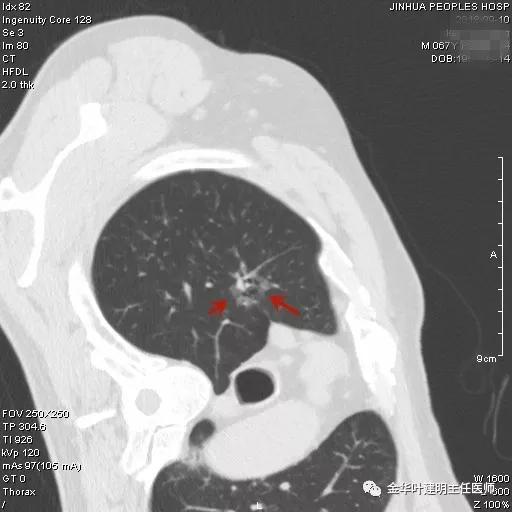

阚某是本院一护士的亲戚,遂找到胸外科叶建明主任医师会诊阅片,考虑是不是肺癌,要不要手术及靶扫描,以及如果需要手术,何时为宜?叶建明仔细阅片并与谭海栋副主任医师商量后,认为其右上肺磨玻璃结节是较为典型的浸润性腺癌影像表现,且与正常肺组织之间并不是界限清楚的,而是呈浸润性改变,但实性成分目前仍不明显,考虑为浸润性腺癌贴壁生长型或腺泡型可能大,应该进一步完善胸部CT靶扫描,以观察病灶细节。手术是要做的,手术方式的确定等靶扫描之后再定。以下为靶扫描影像:

以上诸图示右上叶病灶,是典型的腺癌影像,直径约2.5厘米许

靶扫描以后还发现上叶另外地方还有一磨玻璃结节,约1厘米左右,密度较淡,但瘤肺边界清楚,也是较为典型的腺癌影像: